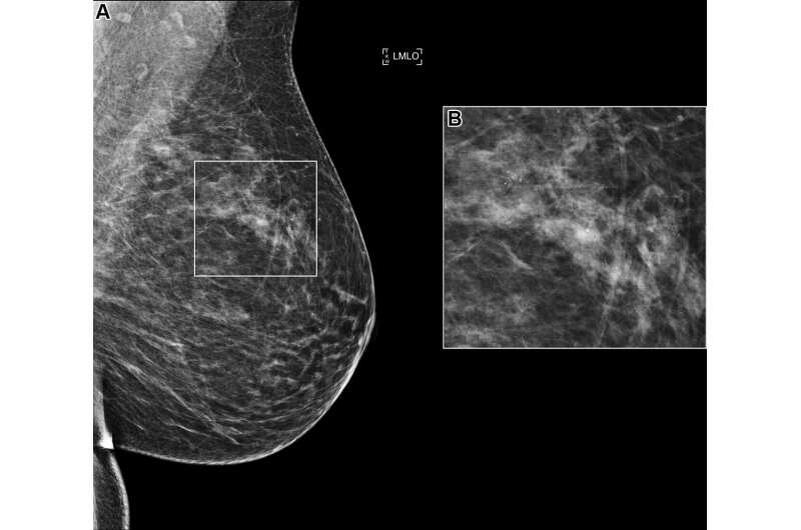

Как алгоритмы со всего мира учились распознавать рак груди — и удивили врачей

В 2023 году RSNA устроило настоящий марафон для искусственного интеллекта — AI Challenge по скрининговой маммографии. Задача? Научить алгоритмы находить рак груди на рентгеновских снимках с высокой точностью, но без излишних ложных тревог.